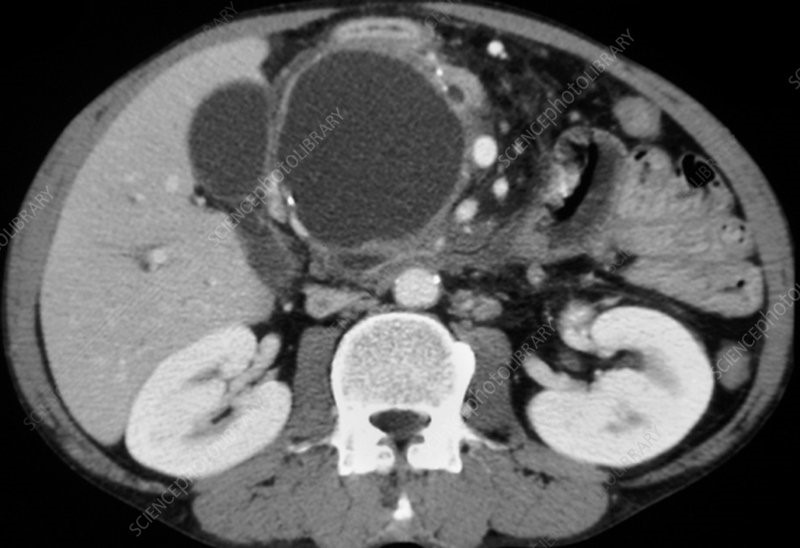

Pode ser causado após um episódio de pancreatite aguda (ingesta de bebida alcoólica e pedra na vesícula), devido ao acúmulo de liquido ao redor do pâncreas após a inflamação, ou devido à ruptura de um ducto pancreático, seja por um trauma ou por pancreatite aguda ou crônica. Possui concentração elevada de enzimas pancreáticas em seu interior. Geralmente se forma dentro de um prazo de quatro semanas do episódio de pancreatite aguda.

A ecografia pode demonstrar a presença do pseudocisto, assim como sinais de pancreatite crônica (calcificações e atrofia do pâncreas) ou aguda, dilatação do ducto pancreático, e aumento do tamanho do pâncreas.

A Tomografia e/ou Ressonância determinam se há pseudocisto do pâncreas, sua localização, assim como a presença de sinais de pancreatite aguda e crônica. Podem ajudar, juntamente com a história do paciente, a diferenciar o pseudocisto de tumores císticos do pâncreas.

A Ultrassonografia Endoscópica (ecoendoscopia) auxilia a determinar se é um pseudocisto ou uma neoplasia cística do pâncreas.

Presença de septações no interior, conteúdo ecogênico compatível com mucina, ausência de sinais inflamatórios, podem sugerir ser um tumor cístico. A ecoendoscopia permite aspirar o conteúdo do cisto. Quando o líquido é aspirado, o material deve ser enviado para cultura para verificar infecção.